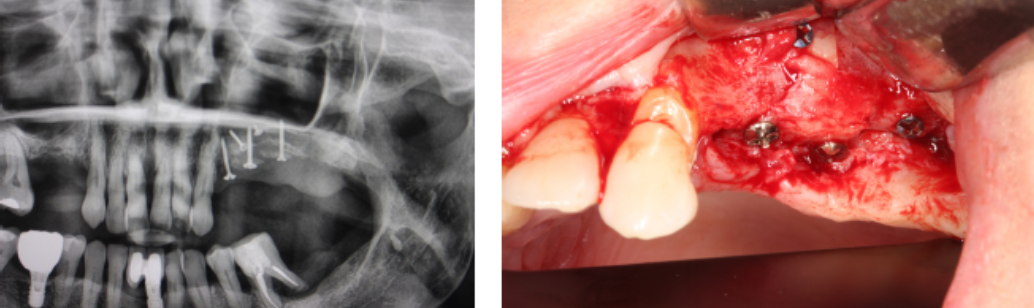

La rehabilitación fija en pacientes parcialmente desdentados con atrofia ósea severa supone un desafío clínico complejo, tanto en el ámbito quirúrgico como protésico. En el presente caso, se llevó a cabo una reconstrucción tridimensional del maxilar atrófico mediante injertos óseos autólogos obtenidos en la cavidad intraoral. El abordaje se realizó bajo un protocolo secuencial que integró el uso de materiales biocompatibles, como membranas reabsorbibles de colágeno y en un segundo tiempo la colocación de implantes junto a pilares Multi fix.